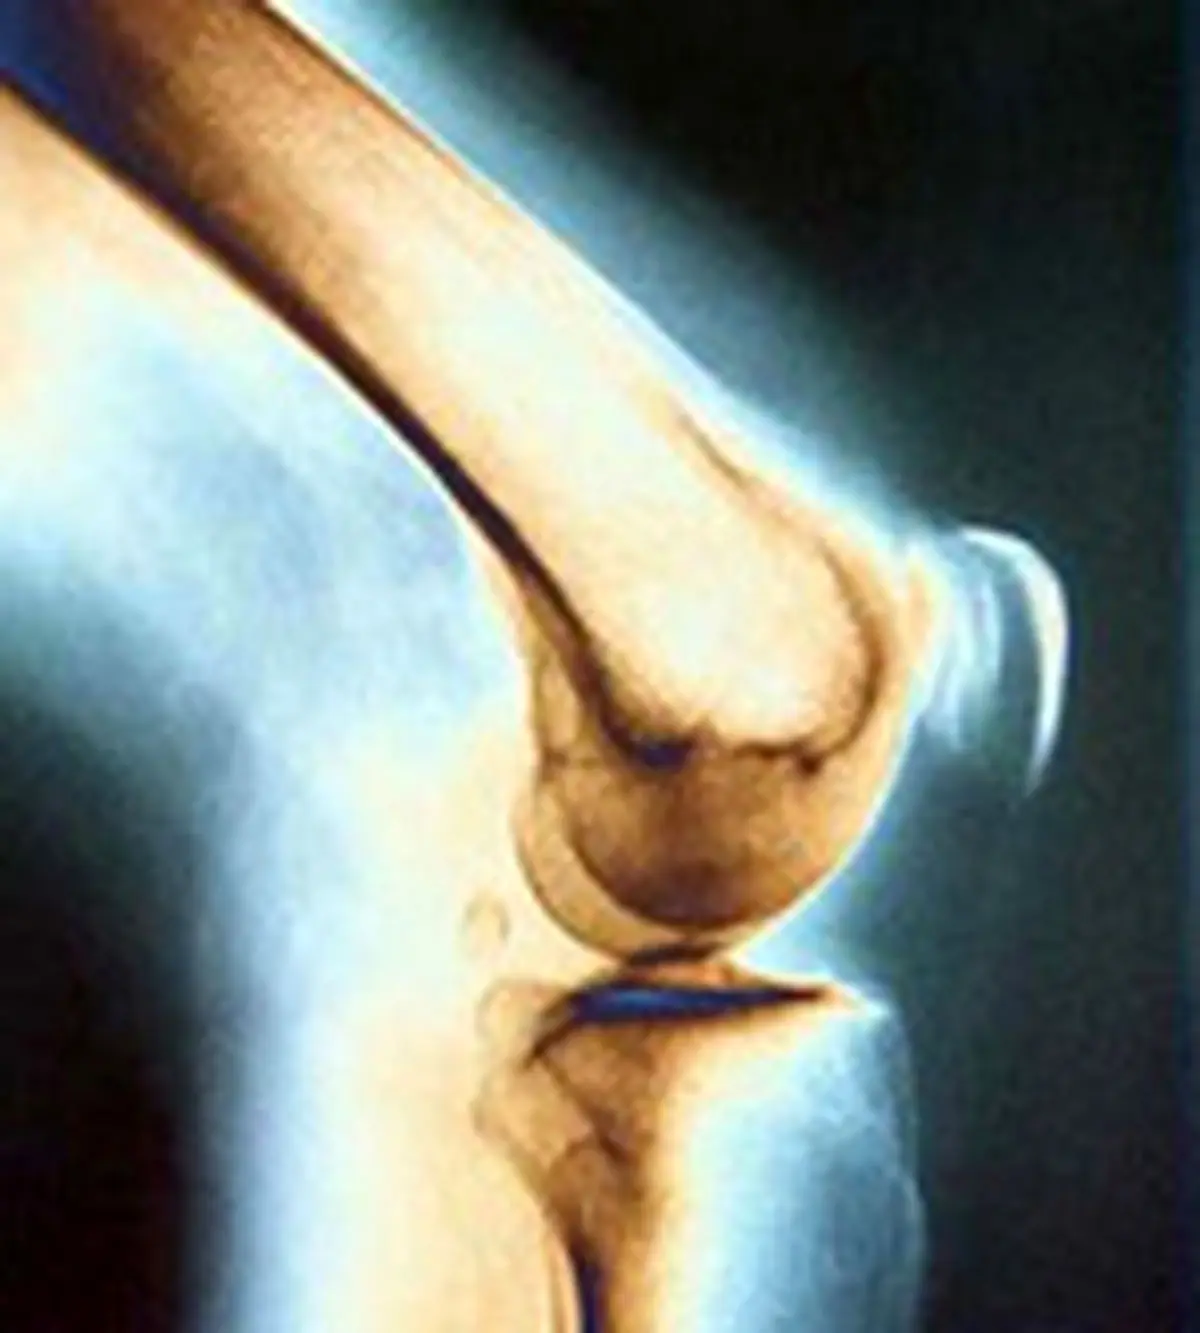

بیماری استخوان مدتها قبل از بروز علائم آغاز میشود. به این علت معمولا با نام فلج کننده خاموش شناخته می شود. تنها راه اطلاع از بروز این بیماری انجام آزمایش است. پزشک شما تعدادی آزمایش برای چک کردن سطح مواد شیمیایی در بدن که بر سلامت استخوانها موثر هستند، انجام میدهد. تجویز پزشک ممکن است شامل مواردی مانند آزمایش خون برای چک کردن کلسیم، فسفر، هورمون پاراتیروئید و ویتامین D، اسکن تراکم استخوان یا اشعه ایکس و نمونهبرداری از استخوان باشد.

بیماری کلیوی افراد را در معرض ابتلا به درد استخوان یا مفاصل، شکستگی استخوان، عفونتها و بیماری پوستی قرار میدهد. عواملی که موجب ضعف استخوان میشوند میتوانند خطر ابتلا به حملات قلبی را نیز به همراه داشته باشد. برای پیشگیری یا درمان بیماری استخوان با پزشک خود مشورت کنید. گامهای سادهای از بروز بیماری استخوان جلوگیری میکنند، مانند تغییر در رژیم غذایی.